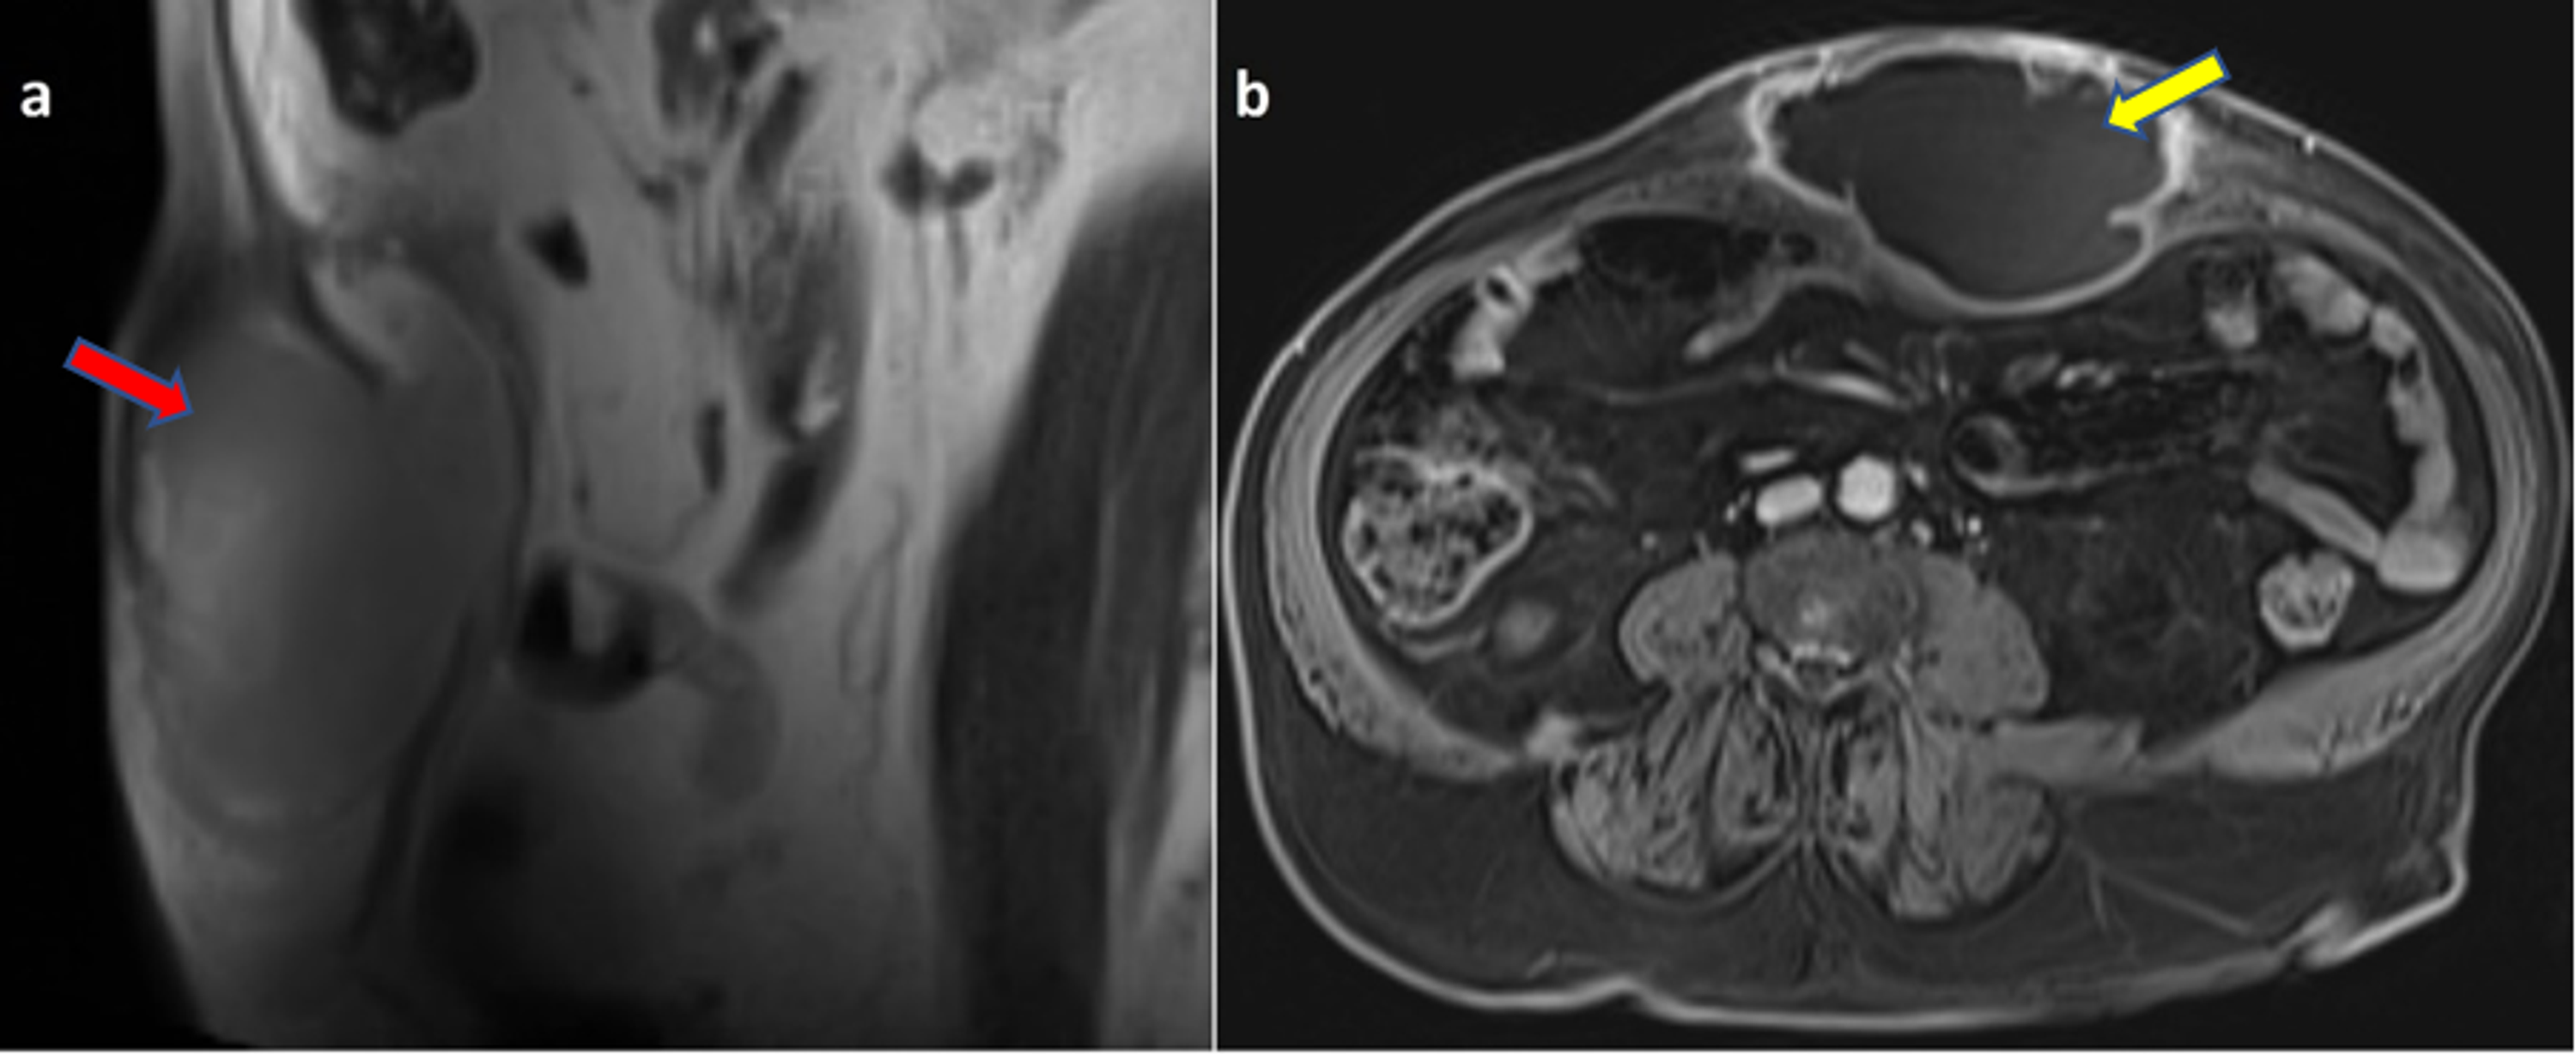

From mavink.com

Abdominal Abscess Mri Abscess Abdomen — an abdominal abscess is when infected fluid (pus) builds up and forms a pocket (or abscess) in your abdomen. Abdominal abscesses can form near the inside of the abdominal wall, at the back of the abdomen, or around organs in. They are a common and serious. abdominal abscesses may form below the diaphragm, in the middle of. Abscess Abdomen.

(a) abscess involving left anterior lower chest wall and upper abdomen Abscess Abdomen — an abdominal abscess is a pocket of infected fluid and pus located inside the belly (abdominal cavity). — an abdominal abscess is a pocket of pus located in the abdomen. — an abdominal abscess is when infected fluid (pus) builds up and forms a pocket (or abscess) in your abdomen. Abdominal abscesses can form near the. Abscess Abdomen.